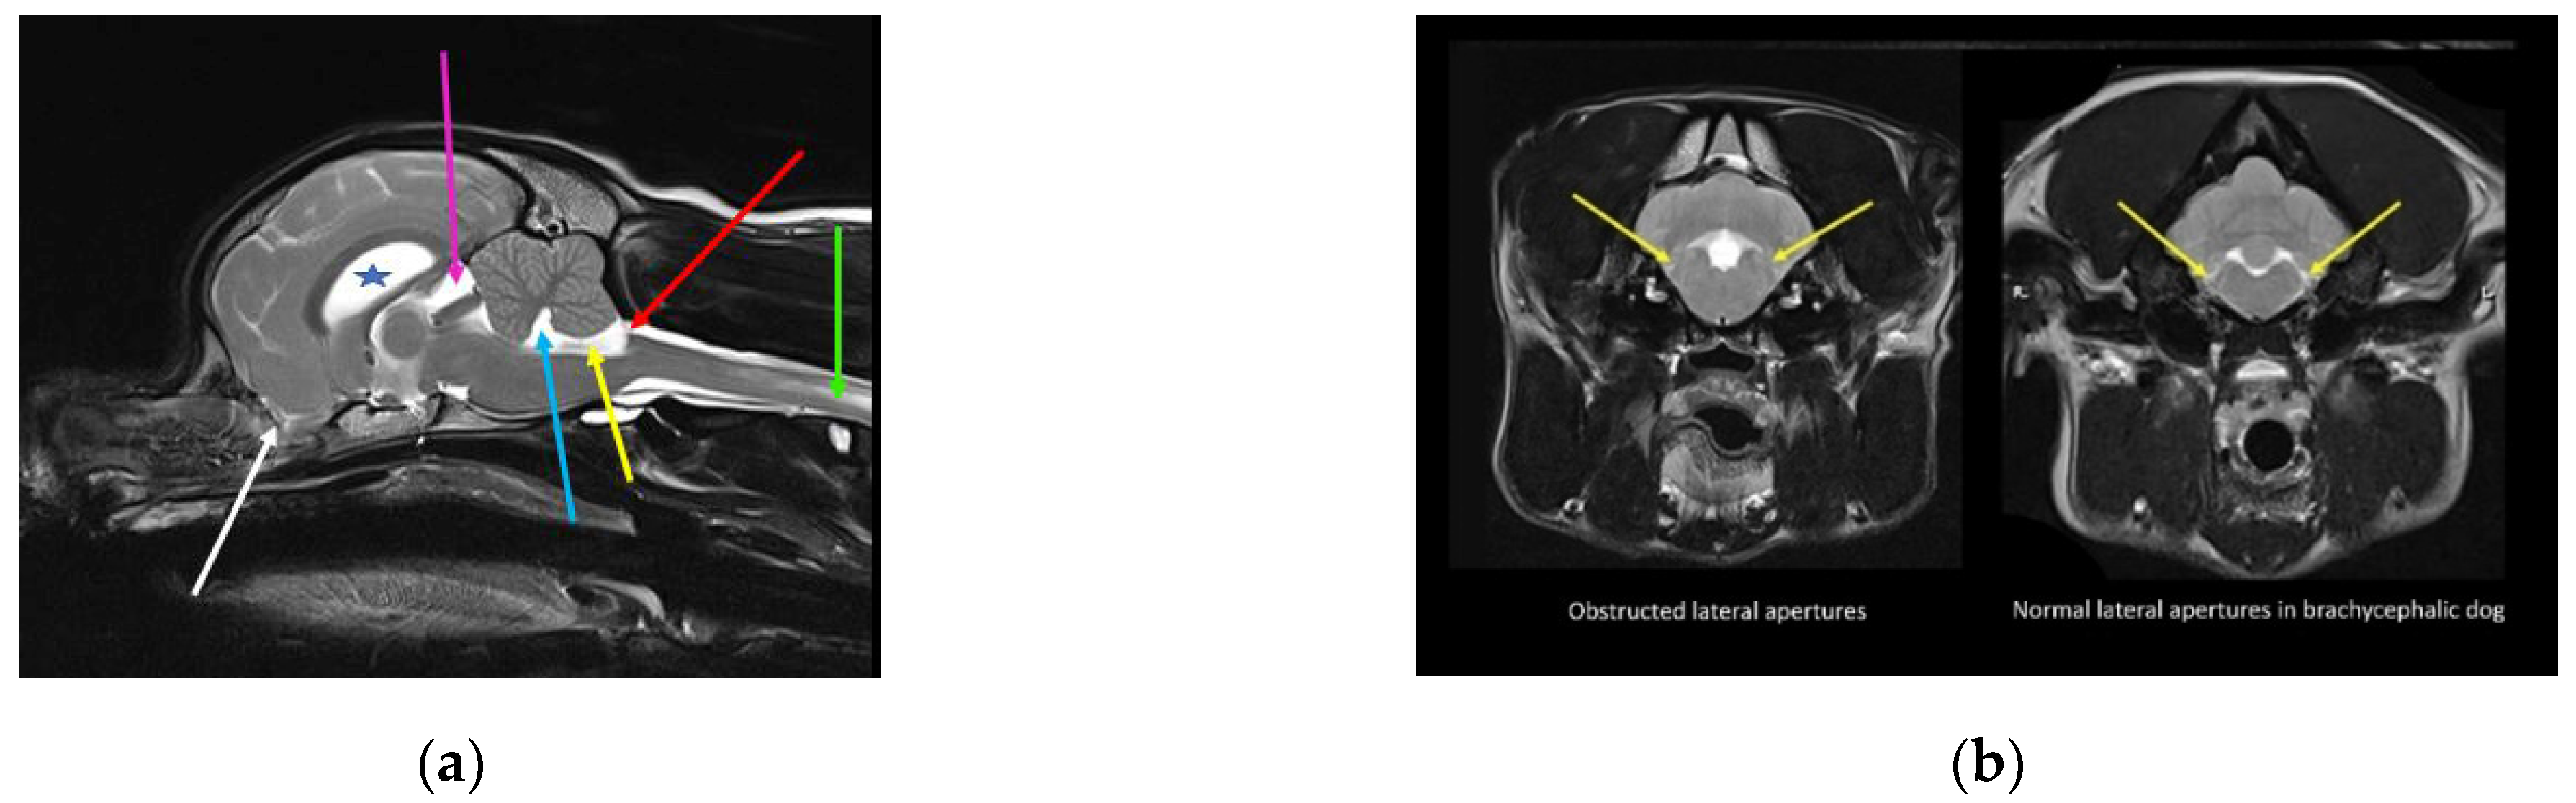

Figure 4.

MRI and CT of a two-year-old female Chihuahua with hydrocephalus, quadrigeminal cistern expansion, and syringomyelia. (a) T2-weighted midsagittal brain and cervicothoracic spine. Yellow star, dilated lateral ventricle; green star, dilated third ventricle; blue star, quadrigeminal cistern expansion with compression of the cerebellum, which is herniated into the spinal canal. White arrow, craniocervical junction abnormality with cervical flexure, angulation of the odontoid peg, and compression of the craniospinal junction. Red arrow, developing cervicothoracic syrinx. (b) Mid-sagittal reformatted CT of the skull and cranial cervical spine. White arrow, craniocervical junction abnormality with cervical flexure, angulation of the odontoid peg, and compression of the craniospinal junction (images created by C. Rusbridge and S.P. Knowler).

The quadrigeminal cistern is a midline dilatation of the subarachnoid space, which is connected to the peri-cerebellar subarachnoid space caudally and medial cerebral hemisphere subarachnoid space laterally. It is dorsal to the third ventricle and mesencephalic aqueduct, but separated from the ventricular system by a thin membrane of pia mater and ependyma [69]. Expansion of the quadrigeminal cistern may be seen in isolation or in conjunction with dorsocaudal expansion of the third ventricle. The term supracollicular fluid collection is used to describe any expansion of CSF-filled spaces rostral to the cerebellum and dorsal to the colliculi and quadrigeminal plate (tectal plate; tectum). Supracollicular fluid collection is a common incidental finding in brachycephalic animals, but may cause clinical signs when sufficiently large enough to compress the adjacent occipital lobe or cerebellum [70] (Figure 4).